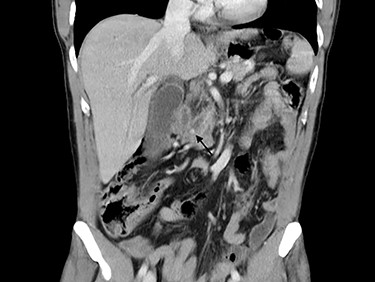

Blood tests performed at admission demonstrated cholestasis and high transaminases. An abdomen computed tomography scan with intravenous contrast was performed, displaying a lithiasic cholecystitis and cholangitis, with a radio-opaque stone in the terminal tract of the CBD (Figs 1 and 2).